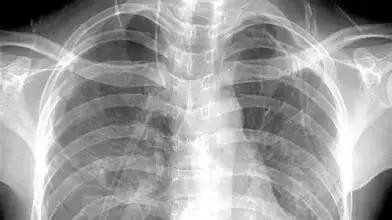

而X线可以透过皮肤,形成骨骼影像,就是大家平时说的拍CT嘛!

想看骨头就用X线: